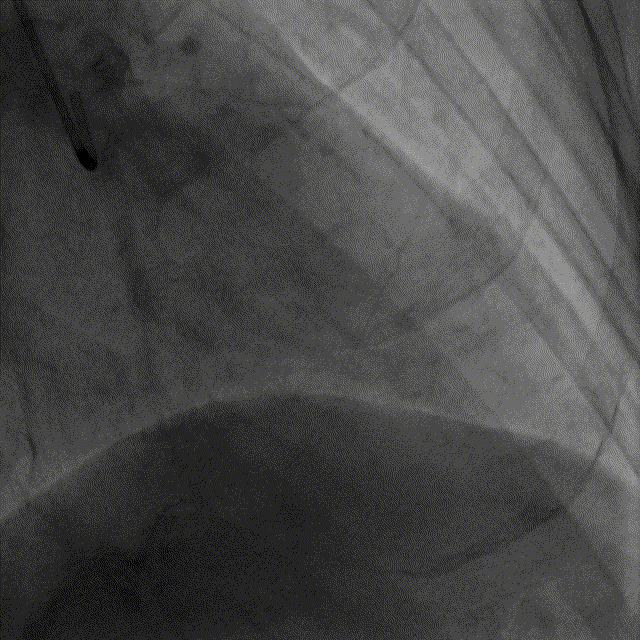

LAD植入支架前

基于OCT的评估,钱菊英教授选取2.5*20mm的球囊对LAD病变进行预扩张,并植入2.5*38mm药物洗脱支架一枚,再选取2.5*15mm的高压球囊于支架内后扩张塑形。复查造影及OCT提示支LAD架贴壁及膨胀良好,手术效果满意。